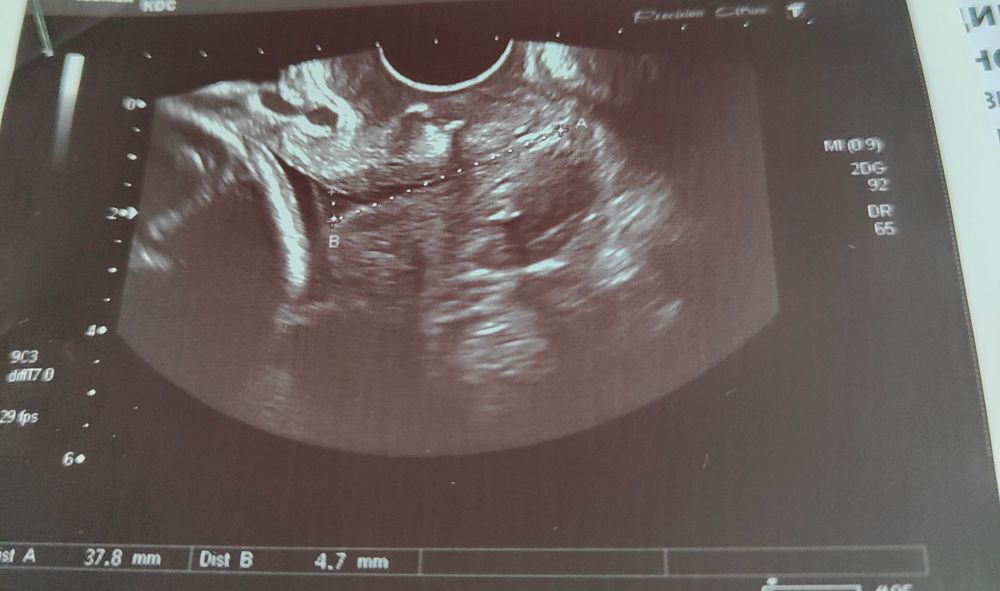

Шейка 37мм внутр.зев открыт

Девочки, всем добрый день. 24,4 нед. Подскажите пожалуйста, шейка 37мм, если зев открыт, значит шейка короче? Не пойму почему намерили открытую часть(см фото)? 3 нед.назад зев был закрыт.

Он не открыт. Он расширен. До 5 мм считается норма.

Открытый внутренний зев описывался как V- и U-образный и определялся при его расширении более 5 мм

Да и по вашему вопросу :считают только закрытую часть. Общую тоже могут измерить, но это ничего не значит. К некоторых, кстати тут читала, зев бывает закрывается. Посоветуйтесь может прогестерон вам назначат локально